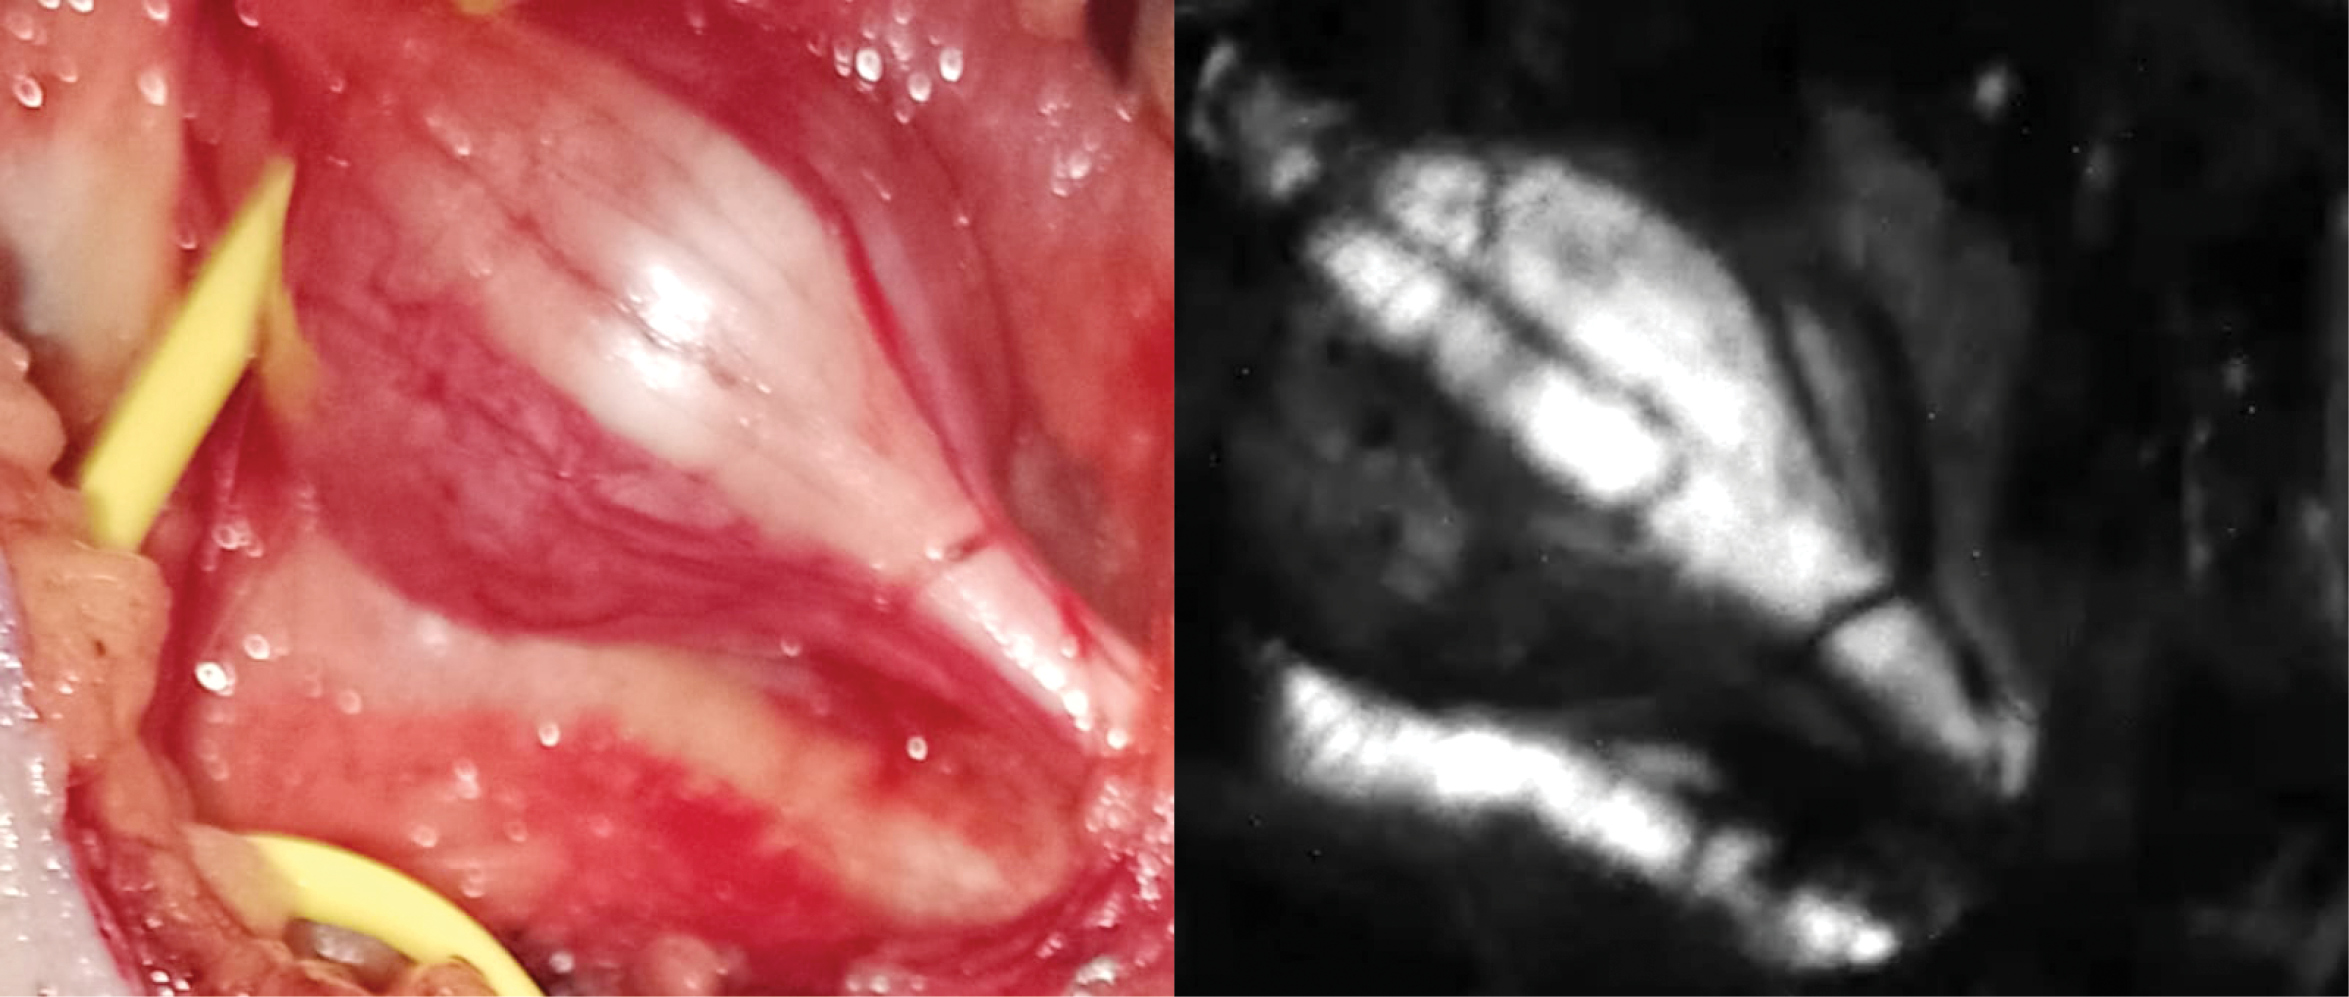

Drs. Dip and Rosenthal started experimenting with ex vivo nerve tissue and different wavelengths, filters and software. “At the beginning of the experiments, working on the bench utilizing a special microscope with a specific wavelength to illuminate nerve tissue, we were able to see the nerves glow—this was really exciting. Then we created a special camera and applied this technology on animals. We were able to visualize nerves but the rest of the tissues we illuminated remained dark. It was then that we realized that we could really differentiate the nerves from other tissues and help prevent or recognize injuries,” Dr. Dip said.

Last year, they published research showing that the intraoperative use of near-ultraviolet light (NUV) was feasible and markedly enhanced nerve visualization in 17 patients undergoing parotid tumor resection, thyroid tumor resection, and surgery for spinal tumors and peripheral nerve damage (Surg Endosc 2022;36:4079-4089). They have now operated on more than 300 patients using this technology.